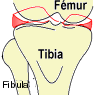

Complexe Articulaire du GENOU

Généralités

C'est l'articulation la plus grosse du corps humain, elle unit la cuisse à

la jambe. Elle est composée de 2 articulations :

- l'articulation fémoro-tibiale, est une double condylienne

complétée de ménisques, elle unit le fémur

au tibia,

Surfaces Articulaires

-

sur

le fémur (épiphyse distale) : la surface

patellaire (old. trochlée fémorale)

s'articule en AV à la face postérieure de la patella (la trochlée

avance plus du côté externe empêchant la luxation de la patella) La

joue externe est plus haute que l'interne. Une gorge sépare les 2

joues qui se prolongent en ARR par les condyles fémoraux séparés à

leur tour en ARR par la fosse intercondylaire. Les condyles

s'articulent en BAS avec les glènes du tibia, le condyle médial est

plus long que le latéral. Trochlée et condyles sont séparés par 2

crêtes intertrochléo-condyliennes,

-

sur

le tibia (épiphyse proximale) 2 surfaces

articulaires supérieures (condyle médial et latéral) séparées d'une

surface en forme de sablier non recouverte de cartilage (l'aires

intercondylaires ant. et post.) sont articulaires avec les condyles

fémoraux par l'intermédiaire des ménisques.

Le condyle latéral est légèrement plus large mais moins longue que le

médial. Les condyles se relèvent (éminence intercondylaire) près de

leur bord axial au niveau des tubercules intercondylaires.